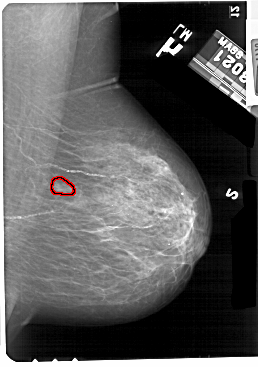

A_1697_1.LEFT_CC

RIGHT_CC LINES 5491 PIXELS_PER_LINE 3676 BITS_PER_PIXEL 12 RESOLUTION 43.5 OVERLAY